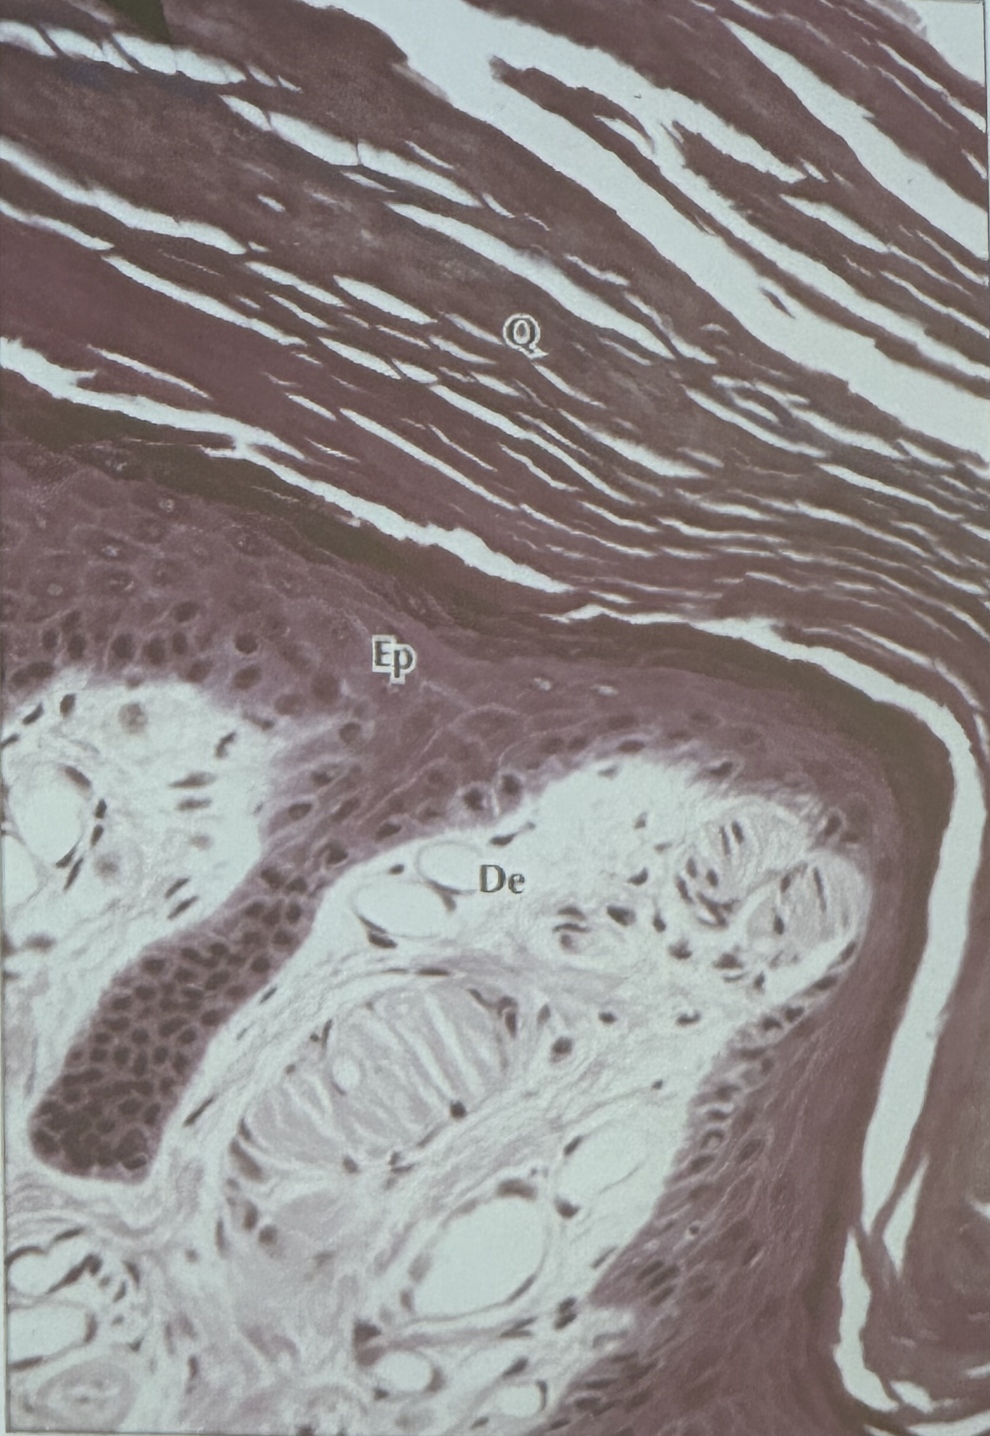

14

Q

A

Epitelio plano estratificado queratinizado